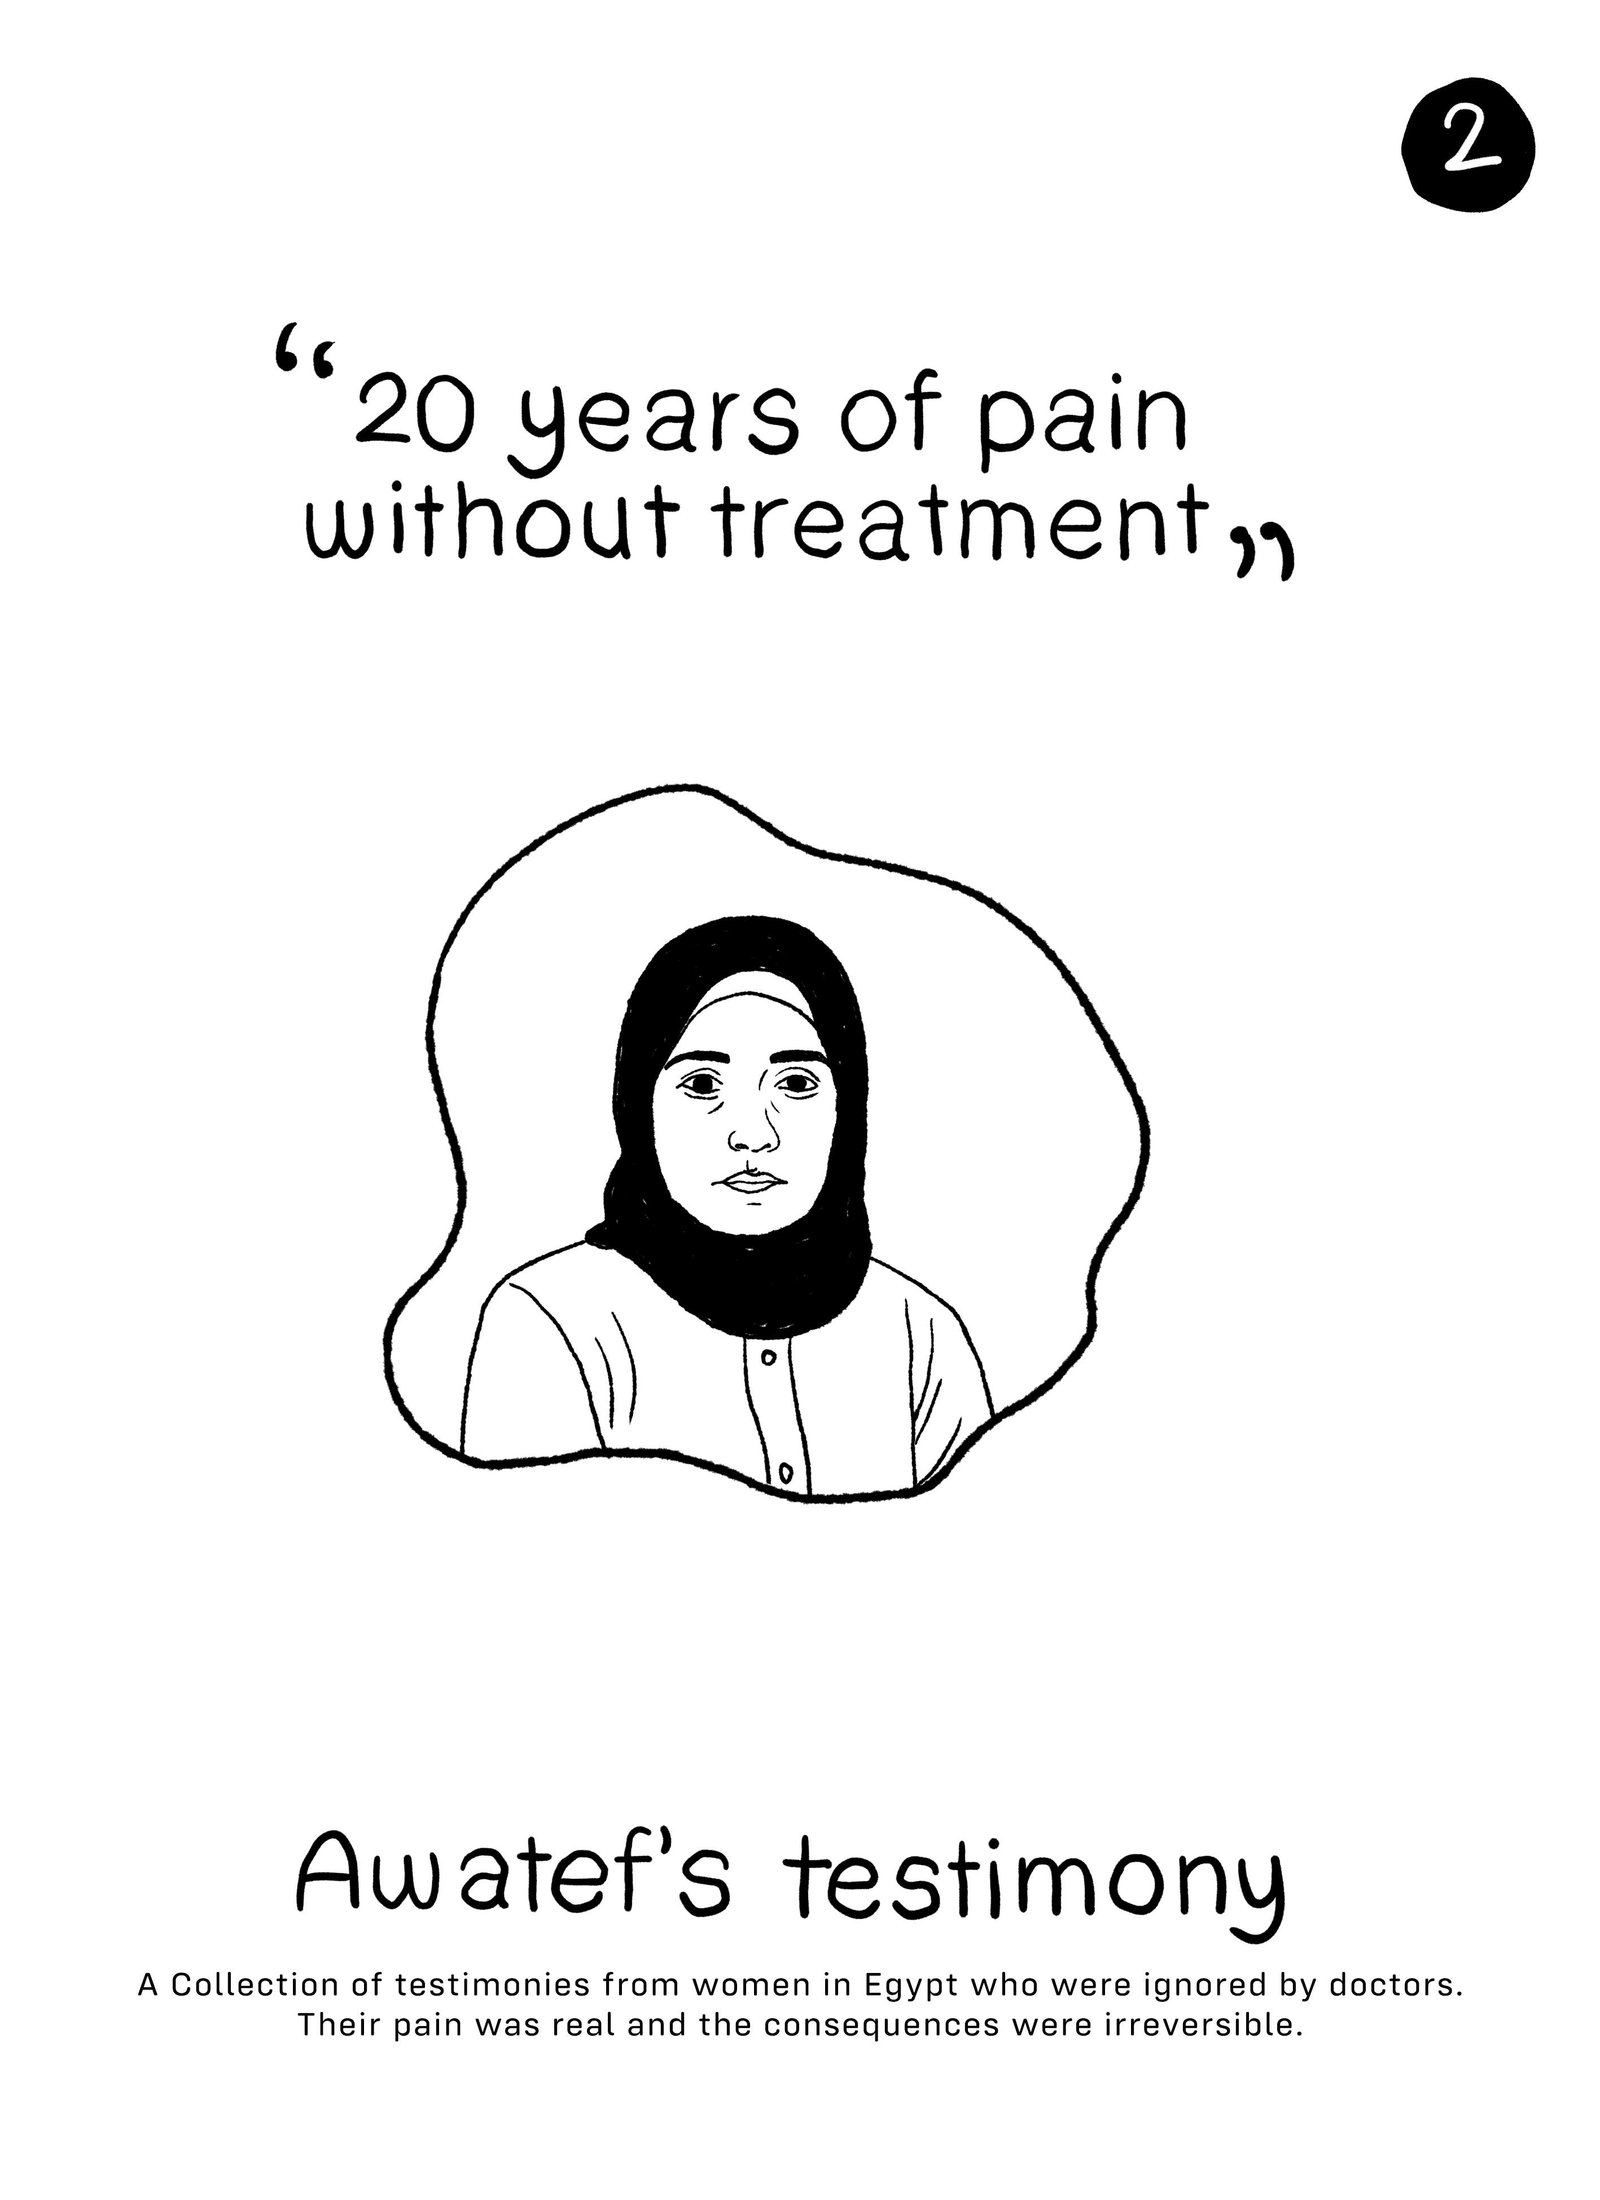

We believe you